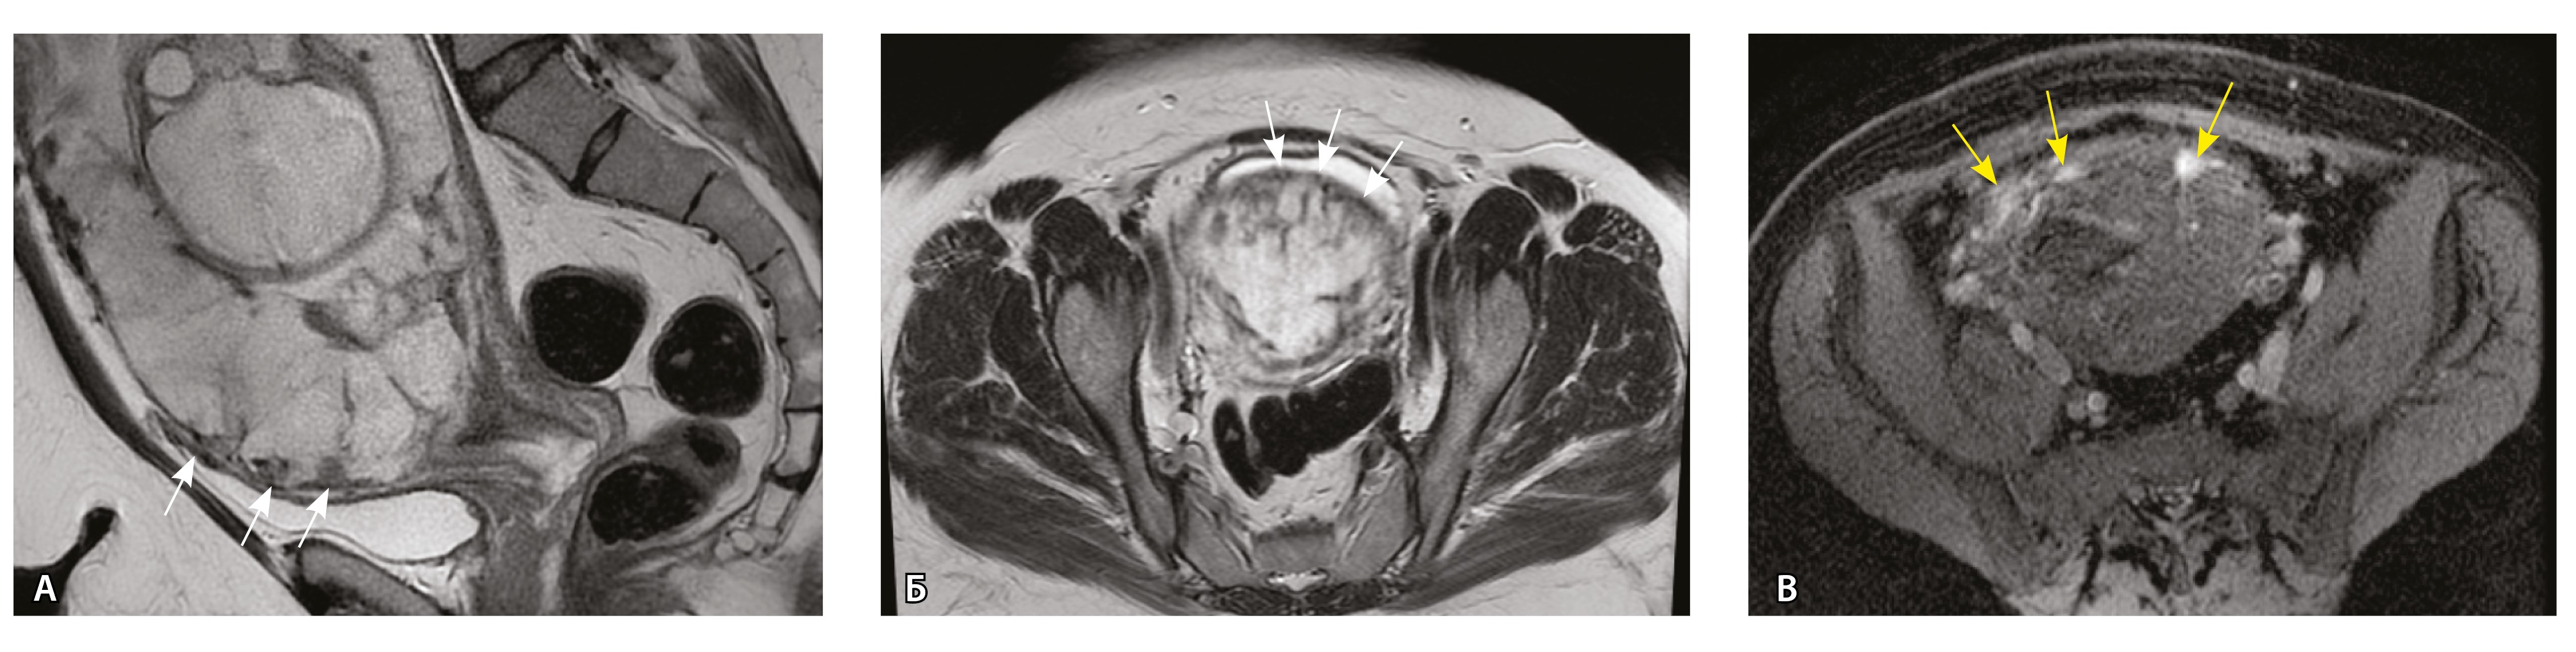

Сосуды 5-го типа. Наличие гиперваскуляризации за пределами матки по данным МРТ, на границе с мочевым пузырем с вовлечением его стенки, сосуды в области перешейка матки, параметрия, в том числе в сочетании с признаками фиброза, наличием рубцово-спаечных изменений и др. Можно предположить, что сосуды 5-го типа являются аналогом pl. рercreta PAS 3b, 3c (рис. 15).

Рис. 15. Беременность 34 недели, pl. percreta, PAS 3b по FIGO (A, Б), PAS 3c по FIGO (В). На магнитно-резонансных томограммах в режиме Т2-взвешенного изображения в сагиттальной (A, В) и аксиальной (Б) плоскостях определяется гиперваскуляризация в области выраженно истонченного нижнего маточного сегмента с распространением сосудов на заднюю стенку мочевого пузыря в области дна (белые стрелки), в область перешейка матки (желтые стрелки)

Данный вариант в патоморфологической картине наиболее сложен для оценки ввиду того, что такие структуры, как параметрий, перешеек матки, стенка мочевого пузыря, обычно не предоставляются в виде макропрепаратов, поэтому визуальные методы, в частности МРТ, могут с большей точностью оценить вовлеченность смежных структур. На микропрепаратах данный вариант инвазии плаценты сочетается с рубцово-спаечными изменениями задней стенки мочевого пузыря с нижним маточным сегментом (рис. 16).